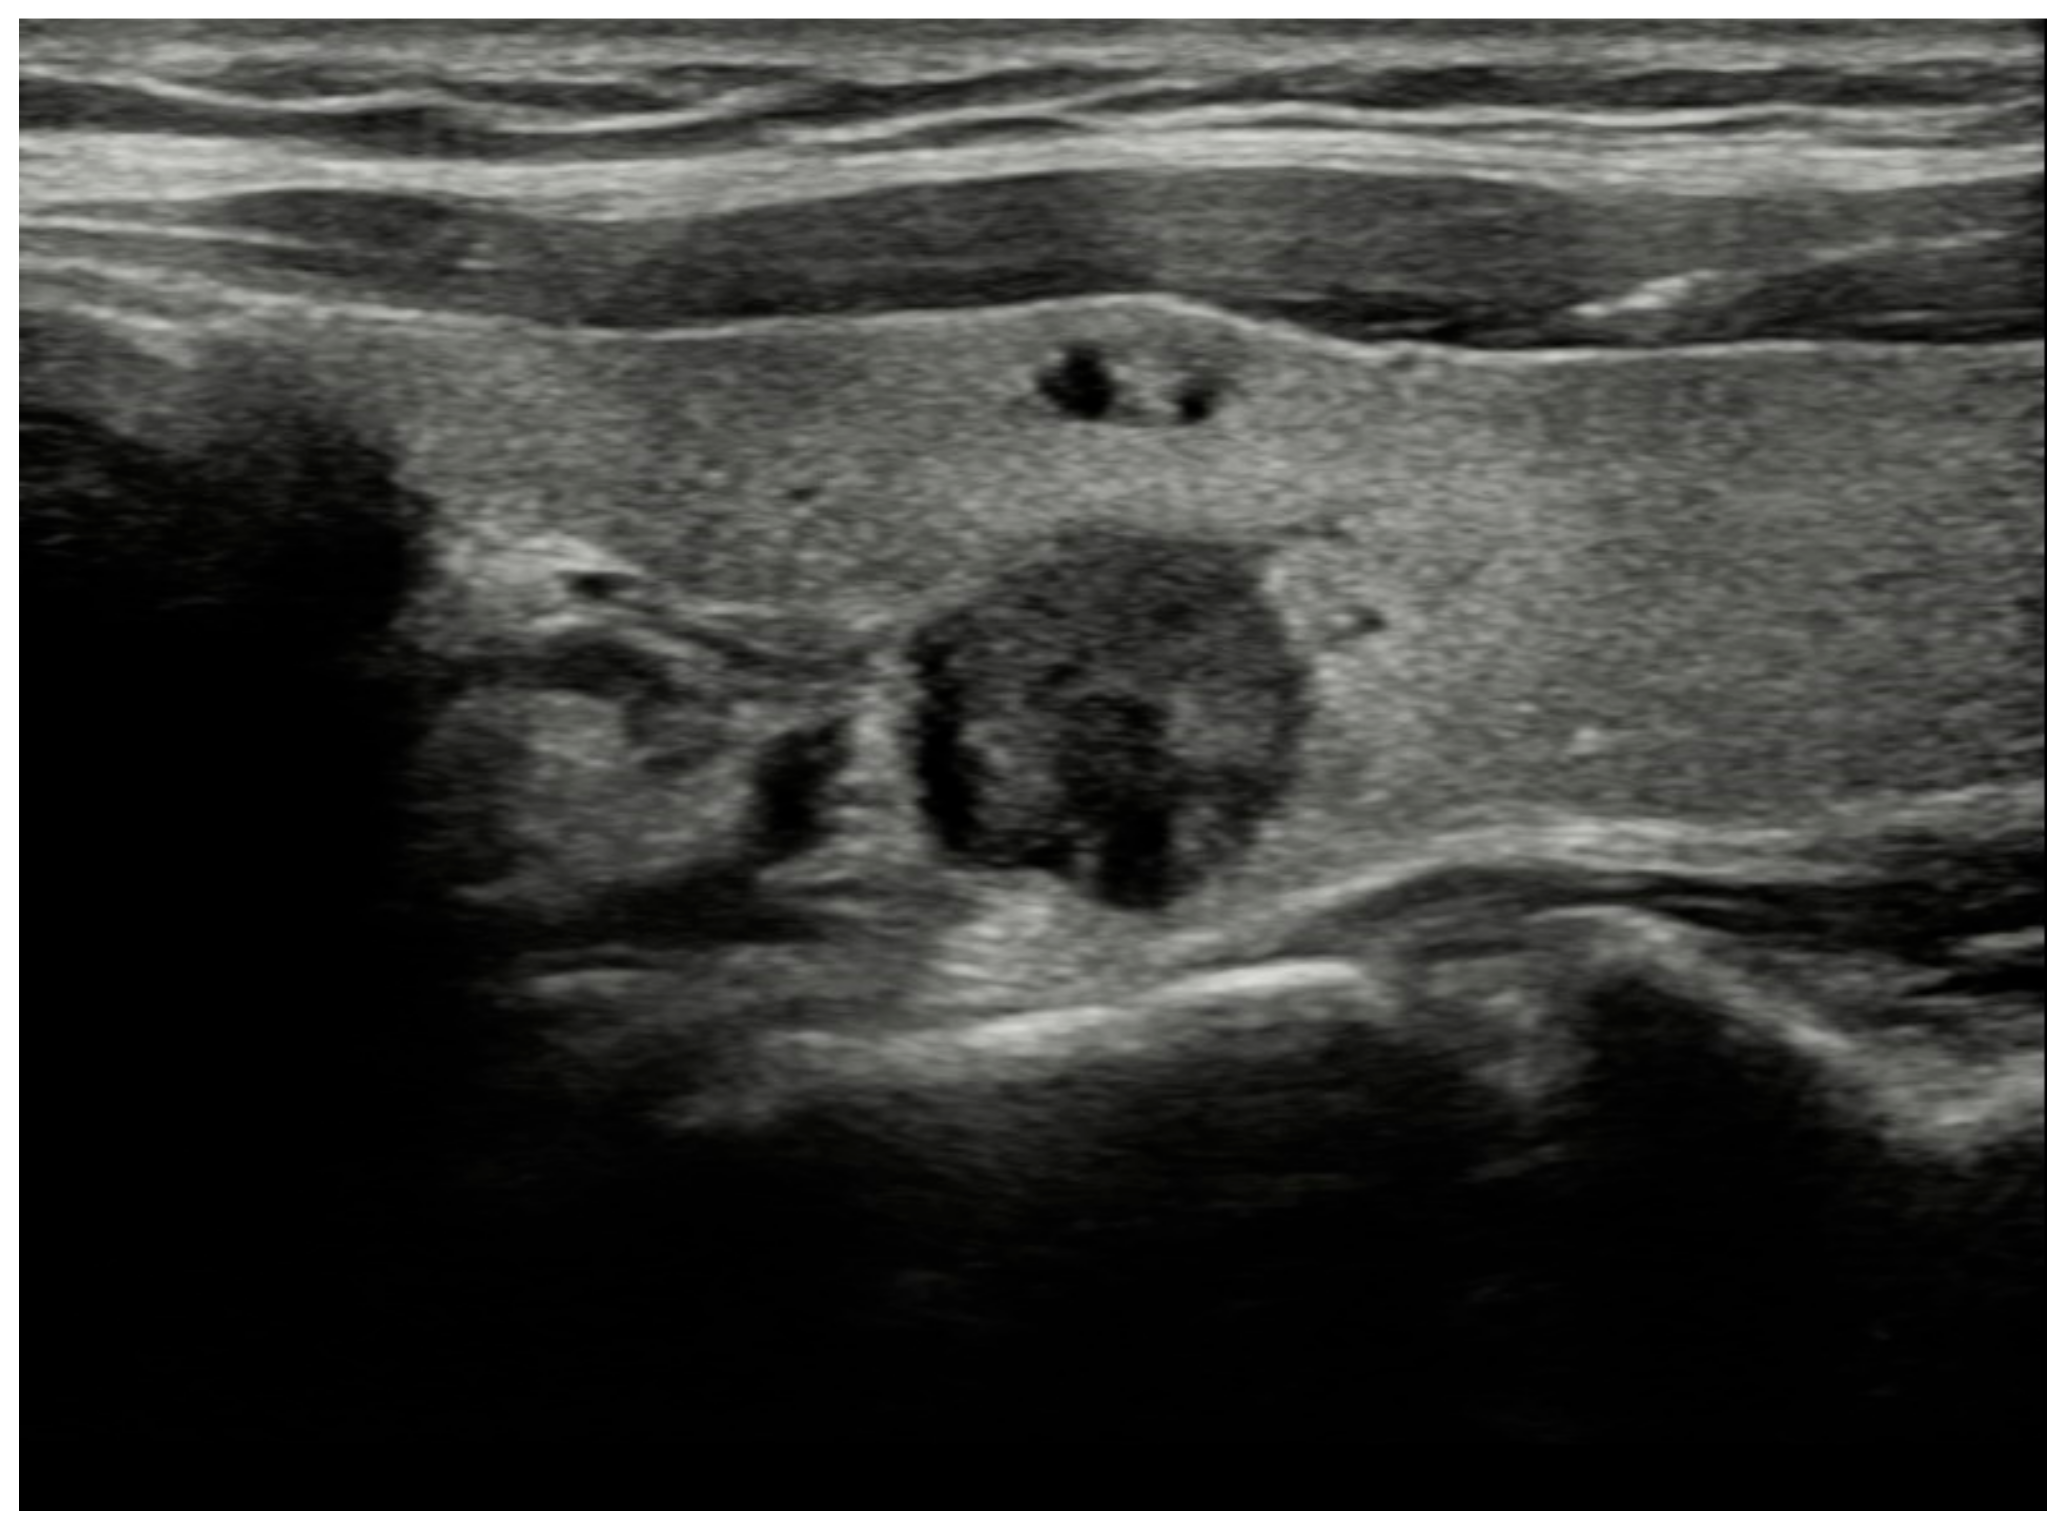

| Size | Composition | Echogenicity | Shape | Margin | Echogenic Foci | TIRADS System | |||

|---|---|---|---|---|---|---|---|---|---|

| ACR | EU | K | |||||||

| 1 | 13 mm | Solid | Hyperechoic | W > T | Smooth | Microcal. | 4 q | 5 | 4 |

| 2 | 12 mm | Solid | Hyperechoic | W > T | Smooth | Microcal. | 4 q | 5 | 4 |

| 3 | 13 mm | Solid | Hypoechoic | W > T | Smooth | None | 4 q | 4 q | 4 |

| 4 | 14 mm | Solid | Hyperechoic | T > W | Smooth | None | 4 q | 5 | 4 |

| 5 | 24 mm | Solid | Hyperechoic | W > T | Smooth | None | 3 q | 3 | 3 |

| 6 | 14 mm | Solid | Hyperechoic | W > T | Smooth | Microcal. | 4 q | 5 | 4 |

| 7 | 17 mm | Solid | Hyperechoic | W > T | Smooth | Rim | 4 | 3 q | 3 q |

| 8 | 12 mm | Solid | Hypoechoic | W > T | Smooth | None | 4 q | 4 q | 4 |

| 9 | 15 mm | Solid | Hyperechoic | W > T | Smooth | None | 3 q | 3 q | 3 q |

| 10 | 18 mm | Solid | Hyperechoic | W > T | Smooth | None | 3 q | 3 q | 3 q |

| 11 | 14 mm | Solid | Hypoechoic | W > T | Irregular | None | 4 q | 5 | 5 |

| 12 | 12 mm | Solid | Hyperechoic | W > T | Smooth | Microcal. | 4 q | 5 | 4 |